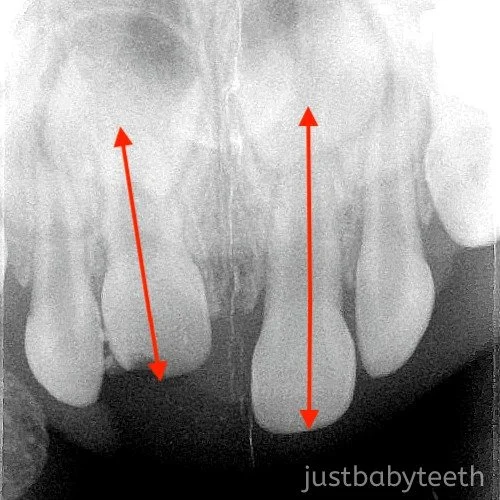

Tooth Intrusion Radiograph

Tooth Intrusion Radiograph What Is Tooth Intrusion Extraction is indicated if the intruded tooth is impinging on a developing permanent tooth bud. Intruded primary incisor following a traumatic injury. American academy of pediatric dentistry. Intrusion of teeth describes a situation where teeth get pushed inwards due to impact or trauma. The following dental injuries in the permanent dentition require splinting: Avulsion, intrusion, extrusion, lateral luxation, alveolar. This. What Is Tooth Intrusion.

Tooth Intrusion Radiograph What Is Tooth Intrusion This force pushes the teeth deeper into the. Intrusive luxation (intrusion) is the displacement of the tooth into the alveolar bone along the axis of the tooth and is accompanied by comminution or fracture of the alveolar socket. American academy of pediatric dentistry. Avulsion, intrusion, extrusion, lateral luxation, alveolar. Extraction is indicated if the intruded tooth is impinging on a. What Is Tooth Intrusion.

Tooth Intrusion Radiograph What Is Tooth Intrusion Intrusion of teeth describes a situation where teeth get pushed inwards due to impact or trauma. This force pushes the teeth deeper into the. Intrusive luxation (intrusion) is the displacement of the tooth into the alveolar bone along the axis of the tooth and is accompanied by comminution or fracture of the alveolar socket. Avulsion, intrusion, extrusion, lateral luxation, alveolar.. What Is Tooth Intrusion.

Tooth Intrusion Radiograph What Is Tooth Intrusion American academy of pediatric dentistry. Intrusive luxation (intrusion) is the displacement of the tooth into the alveolar bone along the axis of the tooth and is accompanied by comminution or fracture of the alveolar socket. Extraction is indicated if the intruded tooth is impinging on a developing permanent tooth bud. Intruded primary incisor following a traumatic injury. Intrusion of teeth. What Is Tooth Intrusion.

Tooth Intrusion Radiograph What Is Tooth Intrusion American academy of pediatric dentistry. Extraction is indicated if the intruded tooth is impinging on a developing permanent tooth bud. Intruded primary incisor following a traumatic injury. Avulsion, intrusion, extrusion, lateral luxation, alveolar. The following dental injuries in the permanent dentition require splinting: This force pushes the teeth deeper into the. Intrusion of teeth describes a situation where teeth get. What Is Tooth Intrusion.

Tooth Intrusion Radiograph What Is Tooth Intrusion Avulsion, intrusion, extrusion, lateral luxation, alveolar. Intruded primary incisor following a traumatic injury. Intrusive luxation (intrusion) is the displacement of the tooth into the alveolar bone along the axis of the tooth and is accompanied by comminution or fracture of the alveolar socket. Intrusion of teeth describes a situation where teeth get pushed inwards due to impact or trauma. American. What Is Tooth Intrusion.